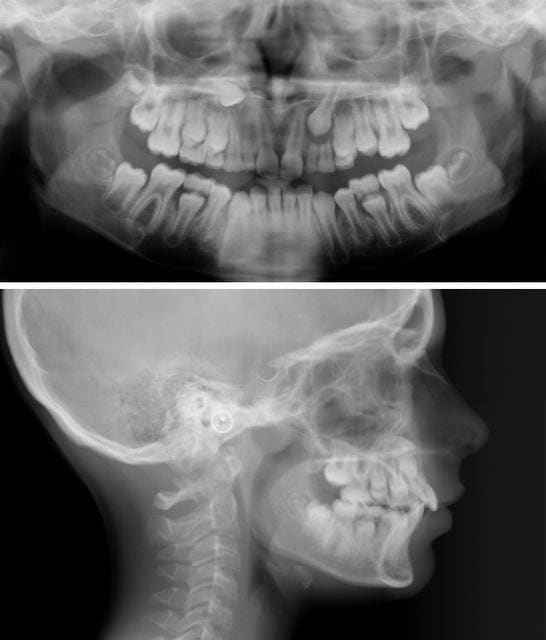

bon alors, sauf erreur on est face à un(e) brachy sévère, qui présente une agénésie des 2 dont la 23 est en train de faire son chemin, dévorant tout ce qui s'oppose à elle (II, III), la 13 a l'air de se plaire dans le palais; tout ceci dans un tableau de cl II 1.

Qu'est-ce-qu'on fait? pas évident avec ces deux documents. Comment est le sens transversal? Sinon, les deux possibilités sont: ouverture ou fermeture des espaces. Si on ferme( perte de 4 mm supplémentaires de longueur d'arcade), vu sa "brachytude", on va éviter d'extraire des prémo mandib, essayer de profiter du Leeway (est-il suffisant?)pour niveler et s'orienter vers la cl II thérap.

Si on ouvre, expansion maxillaire( la mandibule est verrouillée?), on laisse poindre la 23 avec la ptose de 62 63, et tu vas chercher la 13(vestibulaire, palatine?) va-t-elle rhizalyser 52 53 sur son passage, allons-nous devoir faire son chemin?

aux vues des photos, pas d'autre piste: le sens transversal est OK, petite rotation des molaires qui peut nous faire grapiller 2mm si on veut ouvrir les espaces + les quelques mm de la différence ((II +III)-3), si on veut implanter, on va devoir reculer les 6, non?

Je crois que ton cas n'est pas tout a fait similaire a l'autre car les 6 n'ont pas fait de derive mesial. La preuve est la position normale et tres hautes des 8 ainsi que la presence de toutes les dents a l'arcade maxillaire ( a l'exception des 2 manquantes) mais les 52/62 sont la ou presque.

Si il n'y avait pas d'agenesie je serai tente d'utiliser une mecanique de classe II pour reculer les 16/26 et avancer un peu les 36/46 surtout la typologie me permet une petite version supplementaires des incisives inf.

Mais comme les laterales ne sont pas la et afin de limiter les degats et minimiser le travail orthodontique et implantaire plus tard, je choisi plutot la solution de laisser les canines evoluer a la place des laterales, j'attendrai l'arrivee de la 23 ainsi que les premolaires avant de commencer le traitement. Le degagement chirurgical de la 13 peut se faire des que l'arcade maxillaire est preparee et stabilisee.

Daniel,quelles sont les moyens que tu vas employer pour aller chercher la 13?et quand le faire?je ne vois pas d'evolution de la racine sur les radios

Au fait, où se trouve-t-elle exactement cette canine ? J’ai dit précédemment qu’un scan n’était pas absolument nécessaire. Si tu intervenais toi-même chirurgicalement, où irais-tu la chercher ?

Eh bien je vois sa cuspide toute proche de la partie inférieure droite de l'orifice piriforme. Peut être la palpe-t-on très haut dans le vestibule?

Je choisirais donc un abord vestibulaire, très haut dans le vestibule, après avoir fait un scanner ou au moins une téléradio de face.C'est vrai, c'est une radio de plus, mais si je devais aller la chercher moi-même, je la ferais.

Tu as bien vu mon cher Roup, elle est effectivement en vestibulaire haute, même si on ne la sent pas à la palpation. Il serait d’ailleurs intéressant que tu expliques aux autres eugénoliens comment tu as raisonné pour la localiser de la sorte.

Pour ce qui est de la position de la canine, la pointe de la cuspide se projette au dessus du plan bi-spinal sur le téléprofil; sur la pano, elle est immédiatement en arrière du bord latéral droit de l'orifice piriforme.

La couronne de cette canine étant supposée ne pas être dans les fosses nasales, elle se trouve donc dans le triangle osseux sur la photo, sous la corticele vestibulaire; c'est ça Dancha?